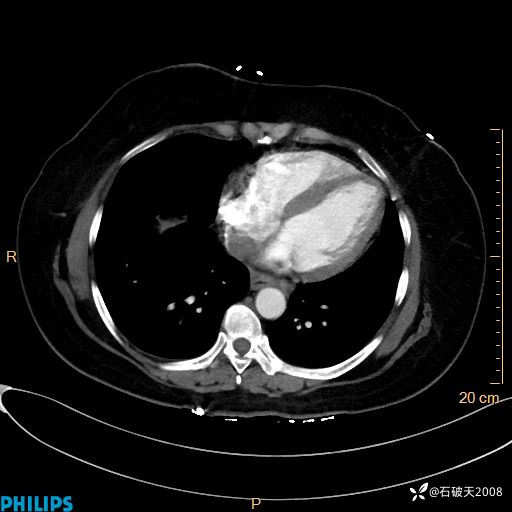

肺窗

纵隔窗